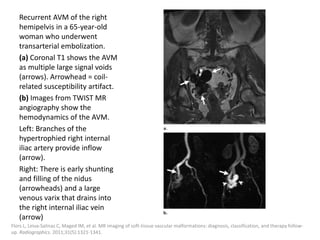

Incidence

Clinical presentation

Imaging features

Treatment

Present at birth in around 0.3% of children.

Traditionally named port-wine stains, they are

the least common and the most superficial of

all low flow vascular malformations.

Histologically, they are composed of ectatic thin-